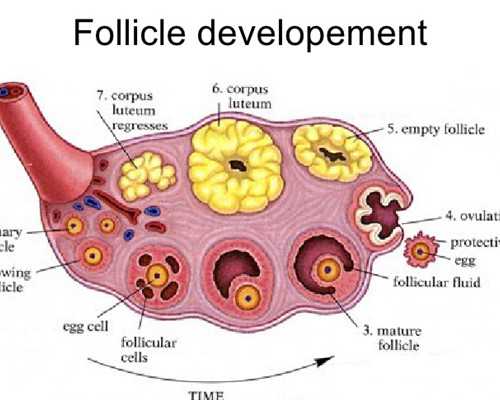

促排卵過程不同

不管是人工授精還是試管嬰兒,他們的促排卵的過程多多少少的都會有所不同,人工授精是可以促排卵,也可以自然來進行排卵,而食管嬰兒必須要選擇超出排卵,也就是說他們在做試管嬰兒的過程當中會一次性提取20多個卵子,這樣的話才能夠配置成各種不同的胚胎,從而在無形當中增加試管嬰兒成功率,有效降低試管嬰兒費用。一次性的促排卵費用,可能價格也在1萬元到2萬元之間。